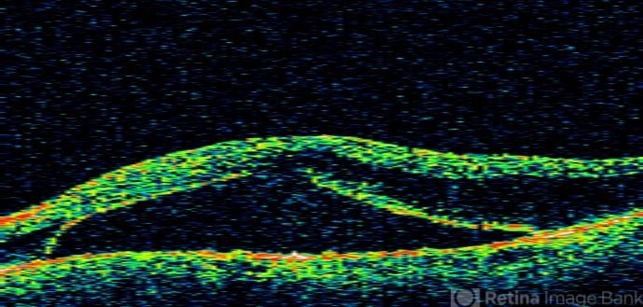

- macular detachment, myeloma

Optical coherence tomography system

stratus - Description

- 84 year-old white male with blurred vision over 2 months. Has incidental BVO.